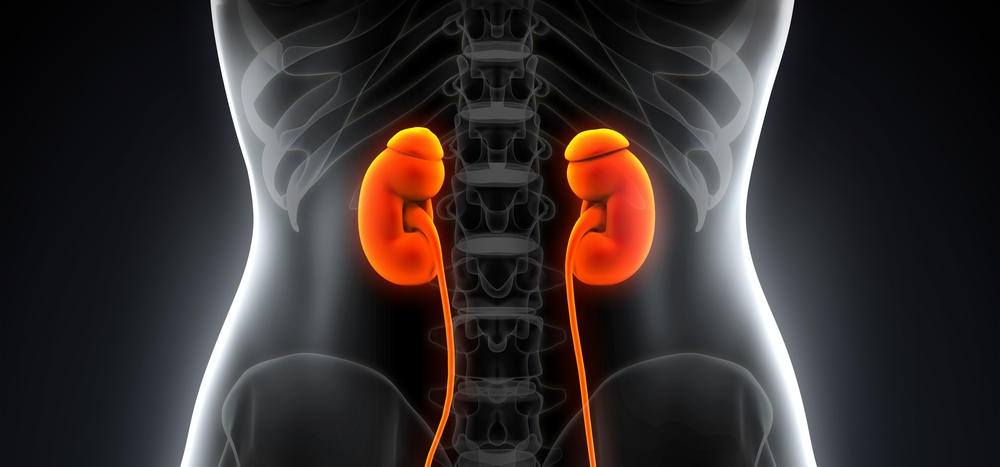

Интраренальная лоханка: рентгеновские снимки и примеры

Раздел: Фотоэссе